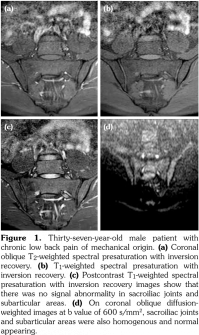

All patients underwent MRI at 1.5-Tesla superconducting eight channel MRI system (Achieva, Philips Medical Systems, Best, The Netherlands) provided with high-speed gradients. The following sequences of sacroiliac joints in the oblique coronal and axial planes as the standard protocol were obtained in the supine positions with a high-resolution phased-array coil: turbo spin-echo T1-weighted (repetition time/echo time, 600/minimum), turbo spin-echo T2-weighted (repetition time/echo time, 2100/80), T2-weighted spectral presaturation with inversion recovery (SPIR) (3100/70), T1-weighted SPIR (600/ minimum) with and without gadolinium-based contrast agents (0.1 mmoL/kg of body weight). All sequences contained lower lumbar spine (Figures 1a-c).

Diffusion-weighted imaging was performed by single-shot spin-echo echo-planar imaging technique with diffusion gradient b values of 0 and 600 s/mm2 (Figure 1d). The following DWI parameters were used: field of view: 25 (right-left) x 32 (anteroposterior) cm; number of excitations: 2; matrix size: 176x176; slice thickness: 4 mm; repetition time/echo time, 8000/minimum; intersection gap: none.

Sacroiliac joints were assessed according to ankylosing spondylitis criteria. Before evaluation of standard MRI protocol, patients’ information was removed from images. Afterwards, two experienced radiologists evaluated the images for the presence of inflammatory activity twice at separate sessions to assess interobserver variability. Following the examination of T2-weighted SPIR, contrast- enhanced T1-weighted SPIR, and DWIs at b values of 600 s/mm2, two radiologists and rheumatologists reached a consensus on the disease activity in the light of positive features of Berlin criteria. The DWIs were transferred to a separate workstation (Phillips, Extended MR workspace, 2.6.3.2.HF3, Netherlands). ADC maps were generated. T2-weighted SPIR images, contrast-enhanced images and diffusion-weighted images with ADC maps were put on the screen side by side. In the disease group, the hyperintense lesions on T2-weighted SPIR images and enhanced focuses on contrast- enhanced images were noted and the same lesions were marked on DWI images and ADC map. A circular ROI with a range of 40-75 mm2 was placed in those areas. In the control group a circular ROI was placed in the subarticular area of joints. Also, the same process was performed for the normal-appearing bone marrow areas near the joints of the disease group (Figure 2). Four standard measurements were conducted from each joint, including two on sacral and the other two on the iliac side for all patients (Figure 3). Additionally, two measurements were conducted from the fifth lumbar vertebra and one from each iliac wing (Figure 4). All measurements were performed twice. ADC values were expressed as square millimeters per second. The r-ADC ratio was calculated by dividing ADC value of subchondral bone or inflammatory lesions to ADC values of the fifth lumbar vertebra and iliac wings.